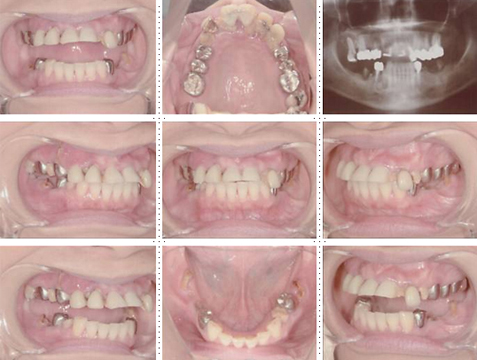

症例2

62才 女性

上顎は総義歯、下顎はブリッジと局部床義歯が装着。義歯は違和感があり、食事も不便を感じ、審美的にも人前にでるのが苦痛に感じていました。この状態を打破するためにも、「インプラント治療に自分の人生を賭けてみたい」という覚悟で来院されました。インプラント手術に対する恐怖心も強くお持ちでした。このような骨幅が狭いケースでは、X線撮影と共にCT撮影による画像診断とインプラント埋入シミュレーションが重要です。

下顎は両側犬歯を残し、他は抜歯。インプラント7本埋入。 上顎はインプラント8本埋入。 インプラント手術を受けられる患者さんは、前の晩眠れない程の不安感、恐怖心を持って来院されます。実際には麻酔注射は痛みを感じず、インプラント手術も痛みも無く、短時間(1本平均3分)で終わるという、当院独自のテクニックにより、2回目からのインプラント手術は気楽になるようです。 前歯は仮歯の段階で患者さん、歯科医、技工士の三者で、審美性・機能性の面から10回以上形態修正を繰り返し検討した後、上・下顎共に前歯・小臼歯はセラミック(MB)クラウン、大臼歯はゴールドクラウンを装着。ご本人とご家族の方にも、「アンチエイジングには、審美インプラント治療が一番効果あり」と大変喜んで頂きました。